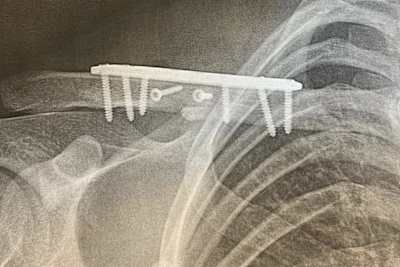

Nach seiner Rückkehr aus Argentinien wurde Gifting bereits operiert. "Die OP ist gut verlaufen", kommentierte er seinen Zustand. "Ich werde jetzt versuchen, so schnell wie möglich zurückzukommen!" Gifting lag nach den ersten 3 Rennen der Saison 2022 solide im Bereich der Top-10. Den ersten MX2-Lauf in Argentinien beendete er auf Rang 7. Trotz seines Ausfalls in der ersten Runde des zweiten Laufs wurde er noch auf Rang 15 gewertet und erhielt dafür 6 WM-Punkte. In der Grand-Prix-Wertung wurde er sogar noch Zwölfter. Zur Erinnerung: Wegen der begrenzten Teilnehmerzahl konnten in Argentinien nicht alle WM-Punkte vergeben werden. Nach 3 absolvierten Rennen hat Gifting nun 67 Punkte auf seinem Konto und rangiert mit 70 Punkten Rückstand zu Tabellenführer Jago Geerts auf Rang 10.